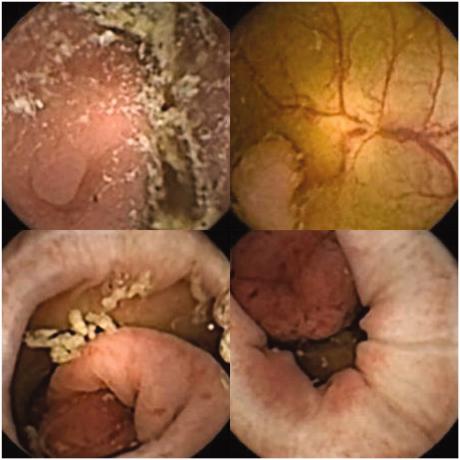

Polypper i forskellig størrelse, farve og morfologi som kamerapillen har taget billeder af.